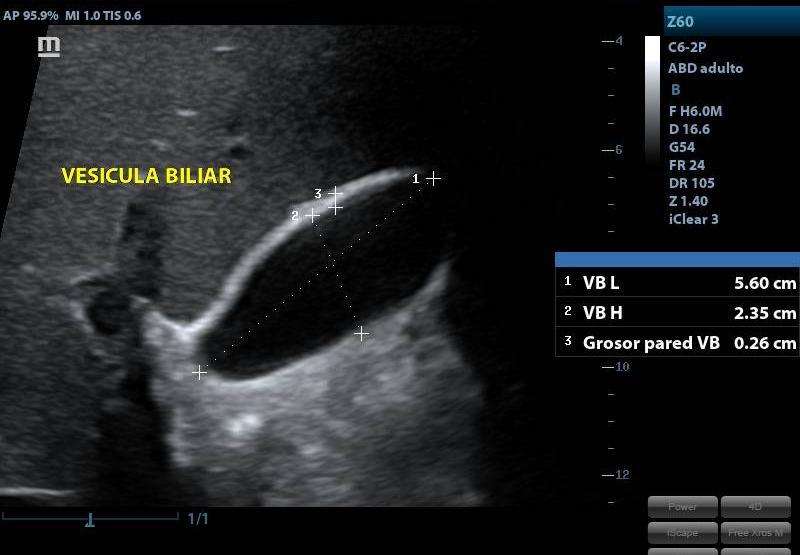

ECOGRAFIA ABDOMEN SUPERIOR

SERVICIOECOGRAFIA

PRESENTACIÓNECOGRAFIA

CONDICIÓNEN AYUNA

TIEMPO20 MINUTOS

TIPO RESULTADOSIMAGENES ECOGRAFICAS

ESPECIFICACIONESSE ESTUDIA: HIGADO PANCREAS VESICULA BILIAR RIÑONES BAZO VIAS BILIARES